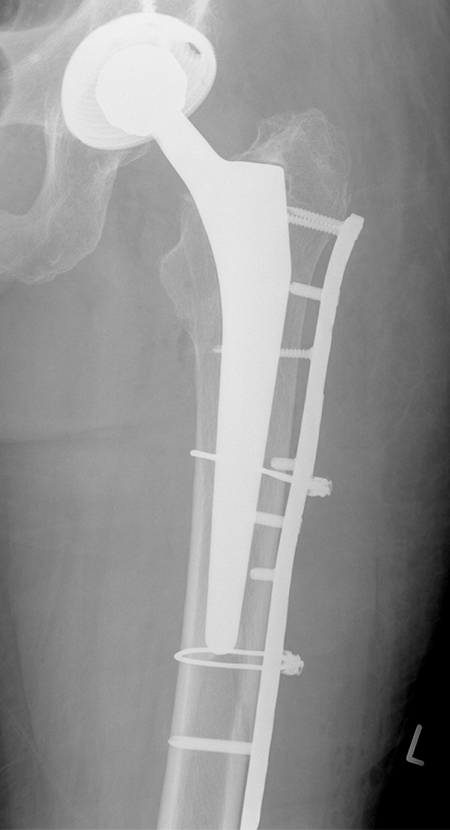

Periprothetische Fraktur - Hüftschaft stabil (Vancouver B1) - liegende Knie-TEP

Knochenbruchbehandlung mit Spezialplatte und Drahtcerclagen um den stabilen Hüftschaft herum

Lange Platte zur Neutralisation der Kräfte